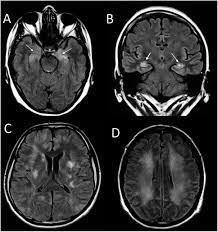

Encefalitis Por Virus Herpes Simple 1 Tras Extirpacion De Meningioma Neurologia

Encefalitis Por Virus Herpes Simple 1 Tras Extirpacion De Meningioma Neurologia from multimedia.elsevier.es